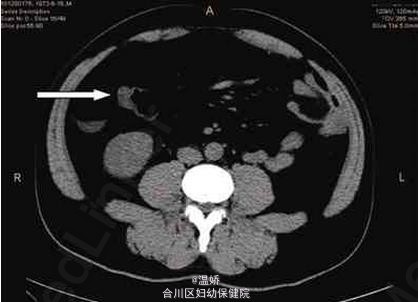

小肠血管脂肪瘤伴胰腺异位 合并小肠憩室套叠

患者,男性,37岁,因“黑便3天”入院。患者3天前饮白酒1斤后出现解黑色糊状大便,每日3~4次,每次约100 g,无明显便血、腹痛、发热、头晕、心悸、冷汗等不适。来我院急诊,查粪隐血(+++),上腹部CT示右下腹结肠肠壁可疑增厚,拟“上消化道出血”收入院。患者10年前胃镜提示胃息肉,饮白酒史10余年,每日约100 g。查体未见异常,考虑上消化道出血,溃疡病可能收入院。